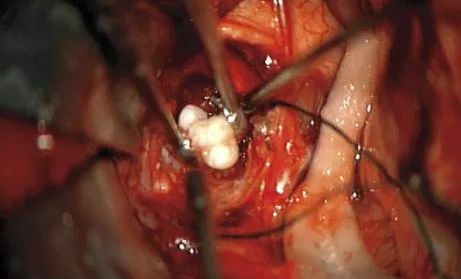

2. El daño cerebral adquirido se considera a cualquier tipo de lesión o cambios que sufre el cerebro por el que surgen alteraciones en el funcionamiento normal, bien por un traumatismo craneal, una isquemia (también conocida por ictus, accidente cerebro-vascular, infarto cerebral), tumores cerebrales, hidrocefalias, anoxias,

1. Tumores

1. TCE Traumas craneoencefalicos

1. Abiertos